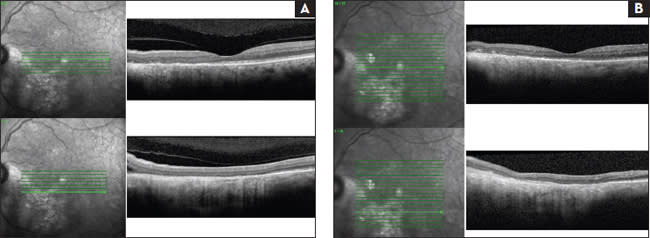

With the use of plaque brachytherapy for posterior uveal melanoma (Figure 2), globe salvage has presented new challenges for the ophthalmologist. The adverse effects of radiation to vital structures, such as the macula and optic nerve, often limit visual function. By three years following radiation treatment, the majority of patients manifest with some stage of this process, which has been difficult to halt once the damage manifests.

Figure 2. Two images of choroidal melanoma: post-plaque treatment (A) and post-plaque treatment with retinal detachment over tumor extending into the macula (B).

The signs of macular edema can be seen with spectral-domain OCT at as early as six months.9 New therapies including anti-VEGF agents, corticosteroids and prophylactic photocoagulation show promise in treatment, especially when diagnosed and treated at the first signs of changes on OCT.16-18

Posterior uveal melanoma is commonly associated with retinal detachments, including exudative, rhegmatogenous and tractional detachment. Studies have shown exudative retinal detachments to range in incidence from 50% to 100% prior to treatment.11,12,19 The accumulation of subretinal fluid results from tumor vascular permeability, as well as dysfunction of the RPE. Fluid often overlies the tumor and tracts inferiorly in a dependent manner (Figure 3).

Figure 3. The same patients from Figure 2. SD-OCT shows subretinal fluid inferotemporal to optic nerve (A) and resolution of the fluid (B).

Following treatment with plaque brachytherapy, exudative retinal detachments (ERDs) tend to improve over time, with a mean of 5.6 months and 90% resolution at one year.12 However, during this time of chronic retinal detachment, the photoreceptors may undergo permanent damage, with the potential for irreversible vision loss. Thus, hastening ERD resolution may prevent long-term visual loss.